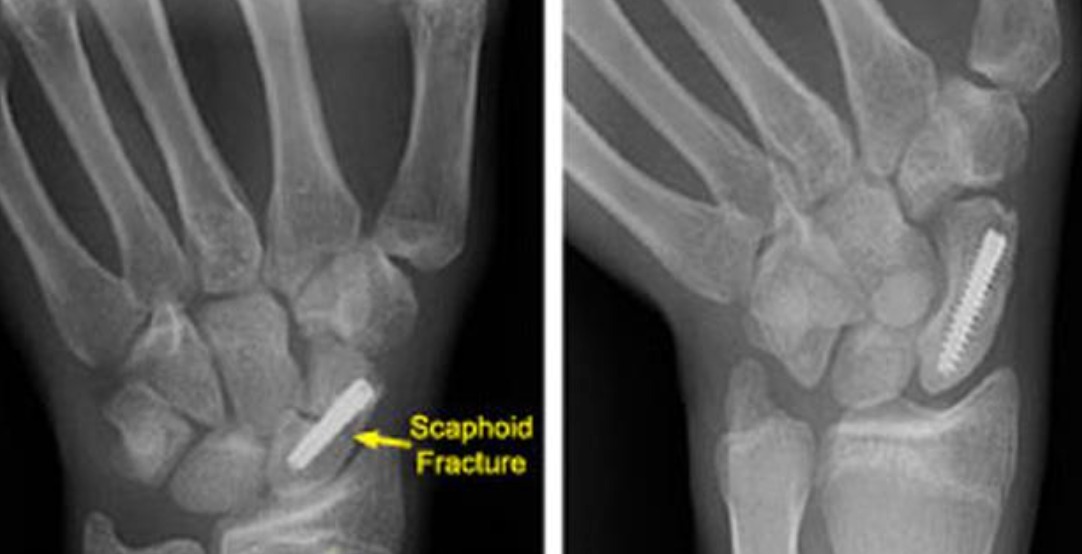

• Percutaneous screw fixation: Increasingly preferred even for undisplaced waist fractures in active patients and manual workers — allows earlier return to work and sport (6–8 weeks vs 10–12 weeks), higher union rate, and avoids the inconvenience and muscle wasting of prolonged casting.

• Open reduction and internal fixation (ORIF): Through a volar or dorsal approach depending on fracture pattern; a headless compression screw (Herbert, Acutrak, or similar) is inserted along the central axis of the scaphoid. Bone graft may be required for fractures with a humpback deformity.